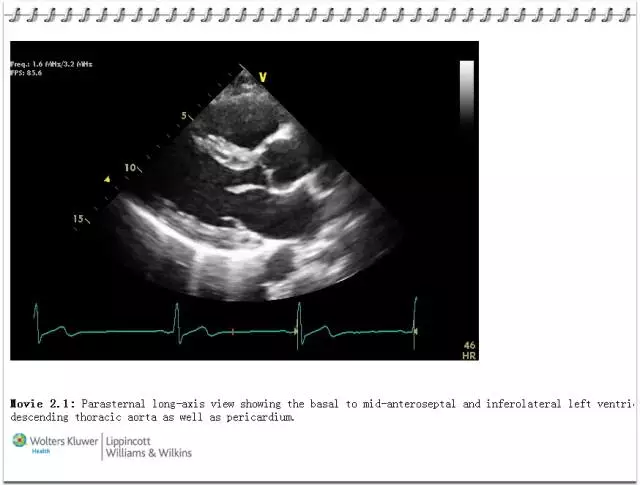

3. 大量高清图片:提高视觉判断和诊断的准确性。

5. 珍贵原版在线资源(一书一码):原汁原味体验内容精华——电子书+动态超声视频影像。